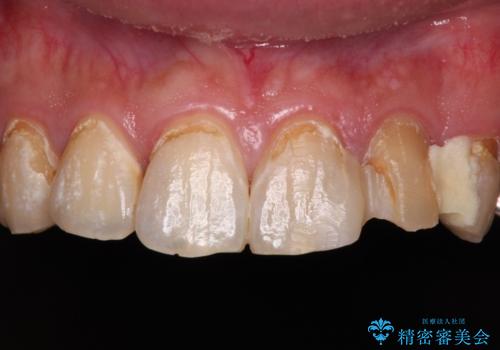

- むし歯の影響で、前歯を見せることが恥ずかしいとのことで来院された患者様です。

全顎的にむし歯が多く、治療が必要な歯はたくさんありましたが、まずは非常に目立つ前歯から処置を行うこととしました。

むし歯は歯肉内にまで進行していると外科処置が必要となりますが、ギリギリの位置でとどまっていたため、速やかにオールセラミッククラウンにて補綴治療することとしました。